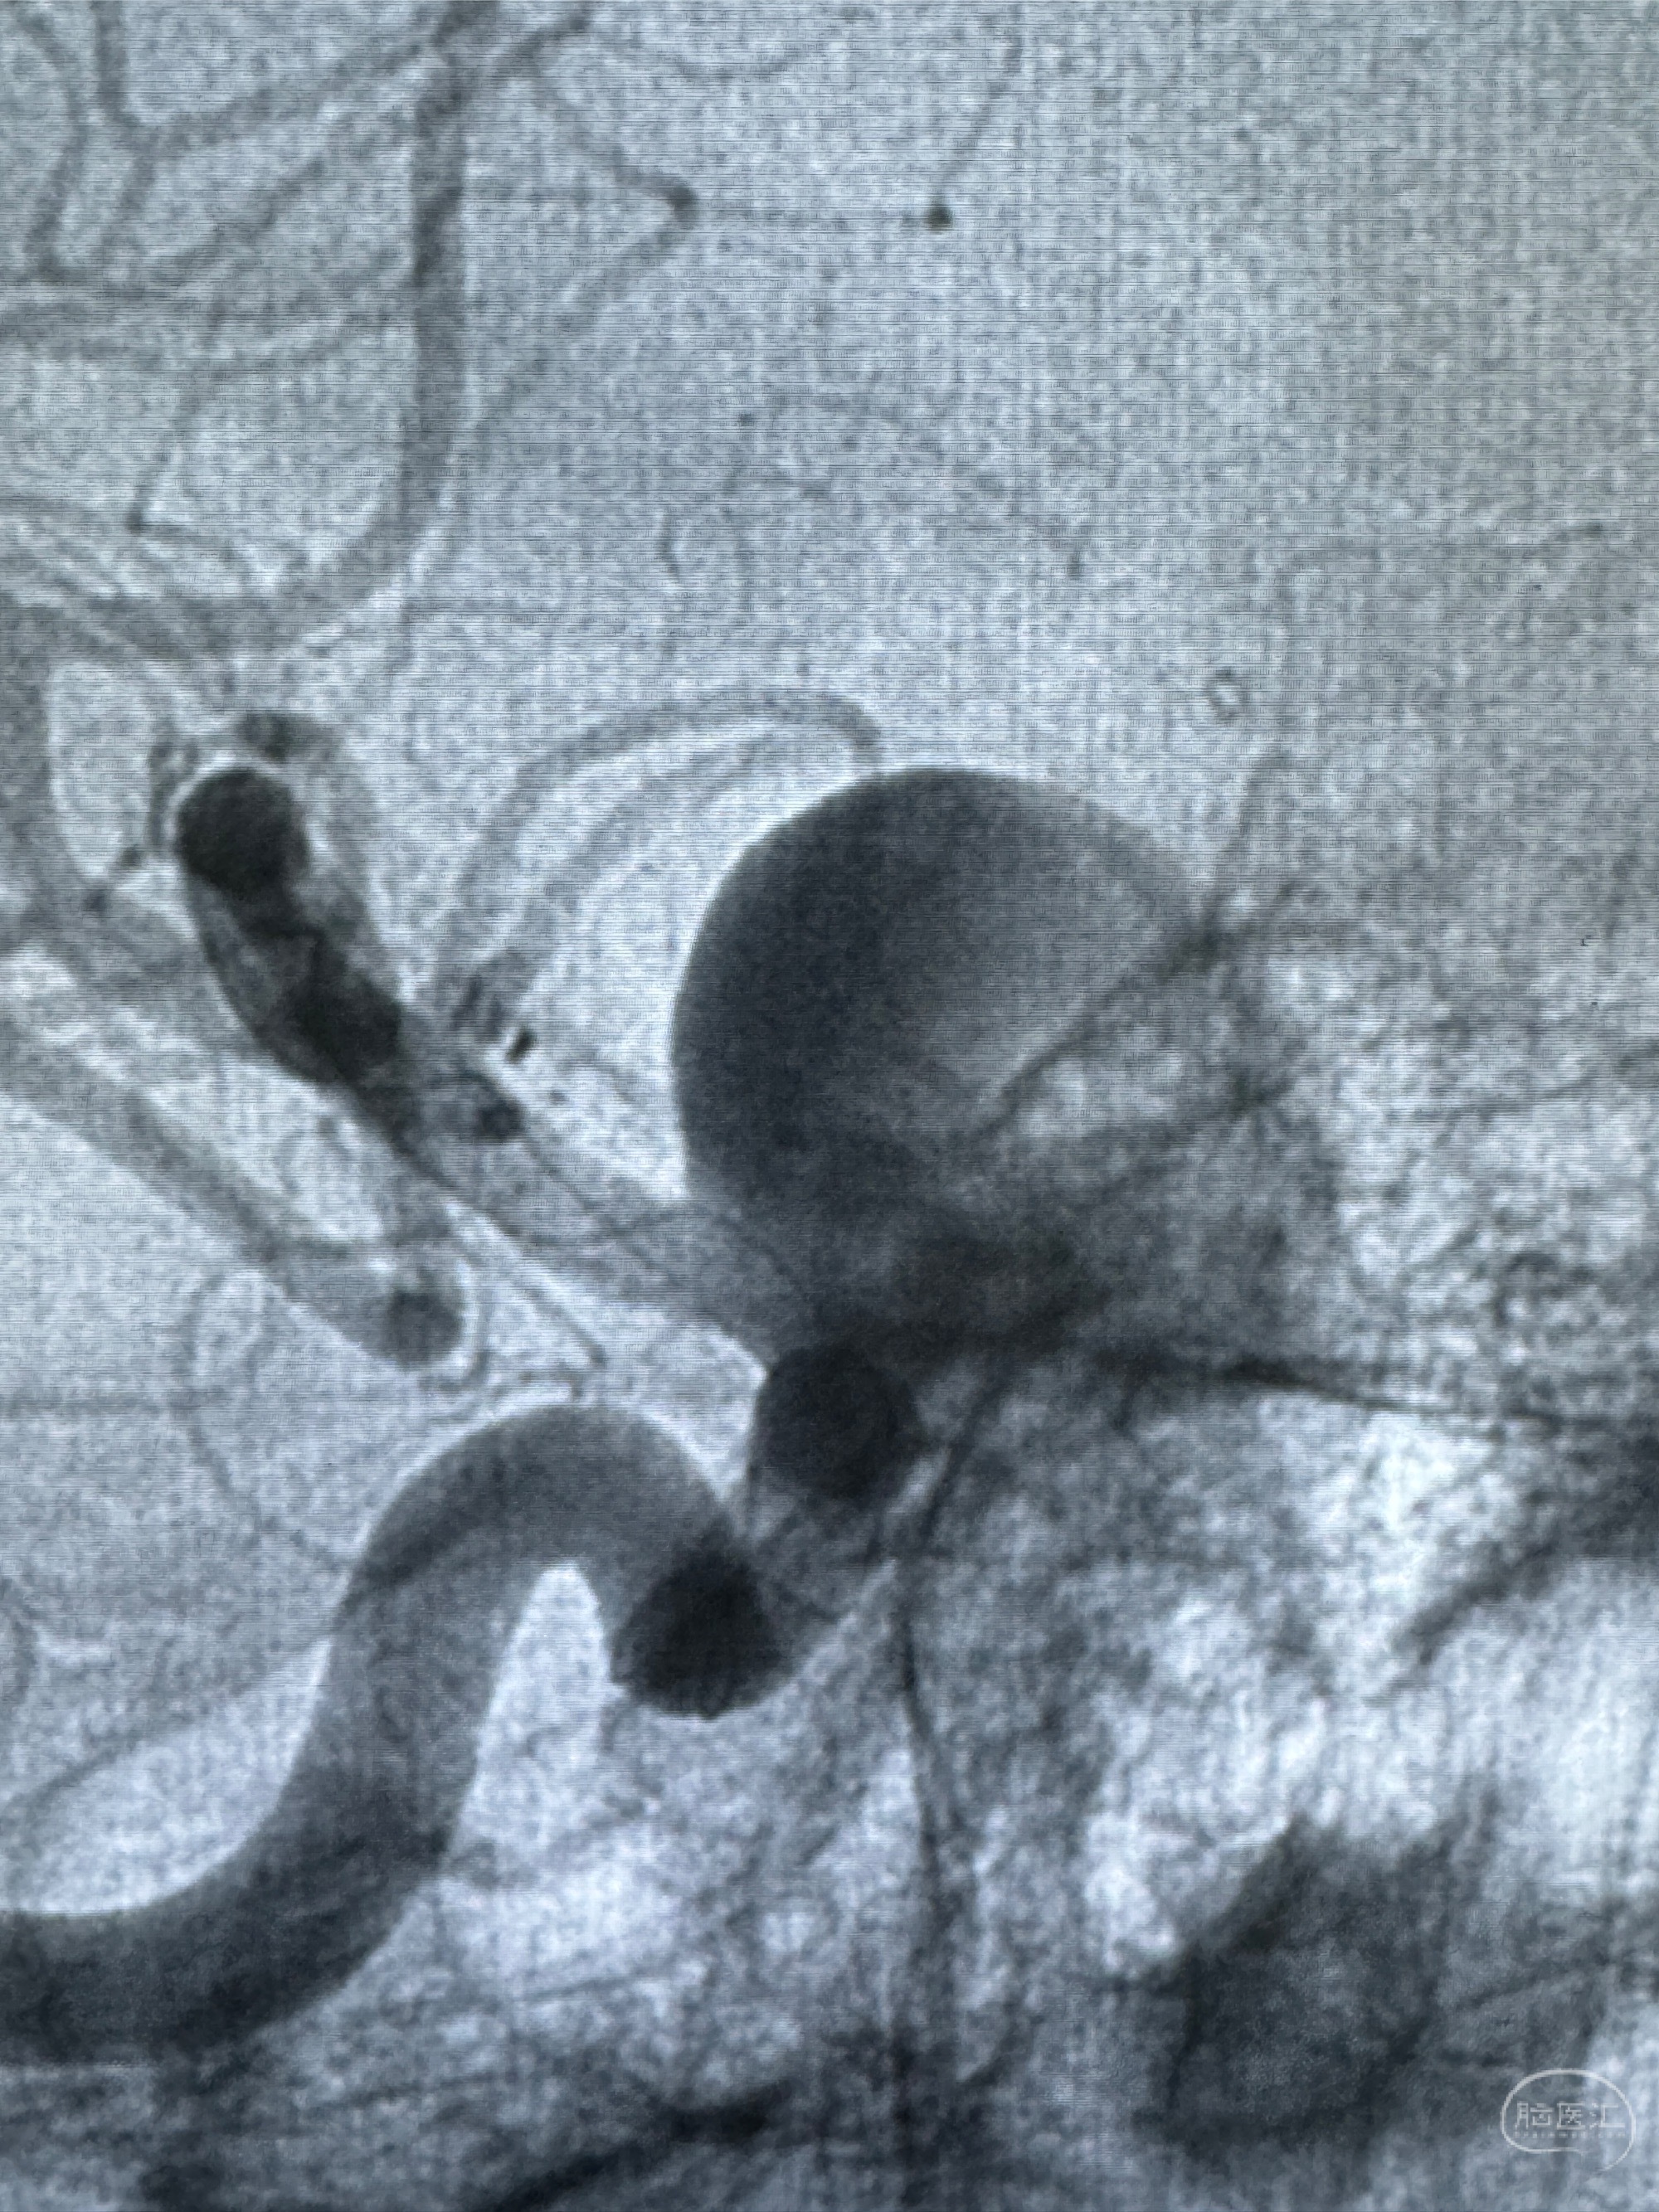

2023-12-27术后第十天复查DSA

支架贴壁佳,但可见射流,咋办?

2024-01-08全麻下再行植入密网支架一枚

Tubridge 4.5-35mm

支架植入顺利,贴壁佳,支架内血流通畅,动脉瘤内血液滞留明显